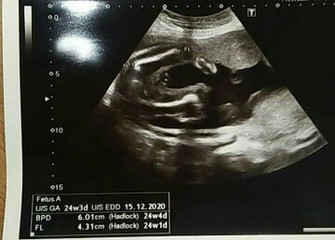

หมอว่าเป็นผู้หญิง

แต่มองไปก็ดูไม่ออกว่าเป็นอวัยวะเพศของผู้หญิง

ปกติคุณหมอจะทำลูกศรให้นะคะแม่ แต่คิดว่าน่าจะอยู่ตรงนี้เพราะว่าโค้งๆ 2 ข้างคือขาน้องค่ะ

น่าจะผู้หญิงค่ะ